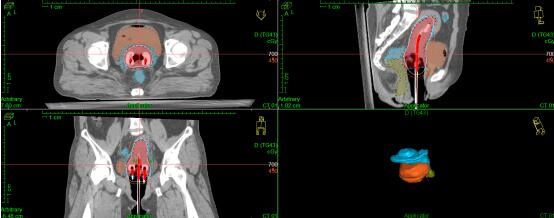

As a characteristic treatment for patients with gynecologic cancer, Brachytherapy has a very long history in our department, radioactive source started from Radium to Cs137 and Ir192. As the local center of Brachytherapy, we have the latest Elekta Flexitron afterloading treatment machine, oncentra brachy three-dimensional treatment planning system and other different kinds of applicators suitable for various situations. Traditional two-dimensional brachytherapy has been applied in our department as well as CT-guided brachytherapy, interstitial brachytherapy and other complex techniques of brachytherapy are emerging as another line of important therapeutics for our patients in the recent two decades.